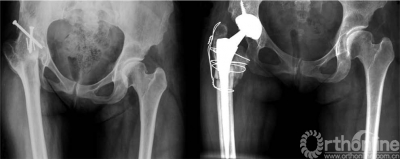

为解决磨损及由此发生的假体松动,出现了各种改良摩擦学特性的界面。在硬质界面中,氧化铝陶瓷对陶瓷关节( 图1) 始终显示出磨损极低、磨损颗粒的生物反应极小。临床上,采用现代金属臼杯的陶瓷对陶瓷THA在以原发性骨关节炎为主要诊断的一般人群中临床结果优异、翻修率极低。在长期随访中,氧化铝陶瓷对陶瓷非骨水泥THA无骨溶解令人鼓舞。因此,在年轻患者使用氧化铝陶瓷界面可能会减少磨损导致的骨溶解和假体松动。这对于年轻患者尤为重要,因为他们的预期寿命长于传统的金属对聚乙烯界面,从而可能面对多次翻修。

本研究前瞻性评价了年龄小于50岁的303名患者(350髋) 使用氧化铝陶瓷对陶瓷THA( 图1)。所有手术均由同一名术者(S.B.M.) 于1997年8月至2009年10月间完成。在此期间总共进行1003例陶瓷对陶瓷全髋置换术,350例(35%) 手术其患者年龄小于50岁。 5名患者(7髋,2%) 未完成最低2年的随访。一名患者(1髋)因与髋关节置换无关的因素死亡。该患者曾因股骨头坏死行带血管胫骨骨移植手术,后行复杂全髋关节置换,由于初次手术后1年股骨柄固定失败而行翻修术(这一翻修手术纳入本研究结果)。四名患者(6髋) 失访,末次随访时Merled’Aubigné 和Postel评分优良( 范围15-18分)。

髋臼侧使用压配式多孔涂层钛臼杯和氧化铝陶瓷平衬( 图1) 。陶瓷衬以18°的锥度固定在金属臼杯内。臼杯平均直径为51.8±3.7(46-60)mm,4%的臼杯需用螺钉辅助固定(表2)。球头使用氧化铝陶瓷, 其中102髋(29%)直径为28毫米,240髋(69%) 直径为32毫米,8髋(2%) 直径为36毫米。337例(96%)非骨水泥THA手术中共使用了七种不同设计的股骨柄假体(表2)。为了更好地重建生物力学,2004年10月后,在187髋(44%) 使用组配型股骨颈设计的假体。2003年8月起,196髋(56%)的植入中使用了以CT为基础的计算机辅助定位。2009年1月起,在26髋(7%, 表2) 采用了机械导航臼杯定位。